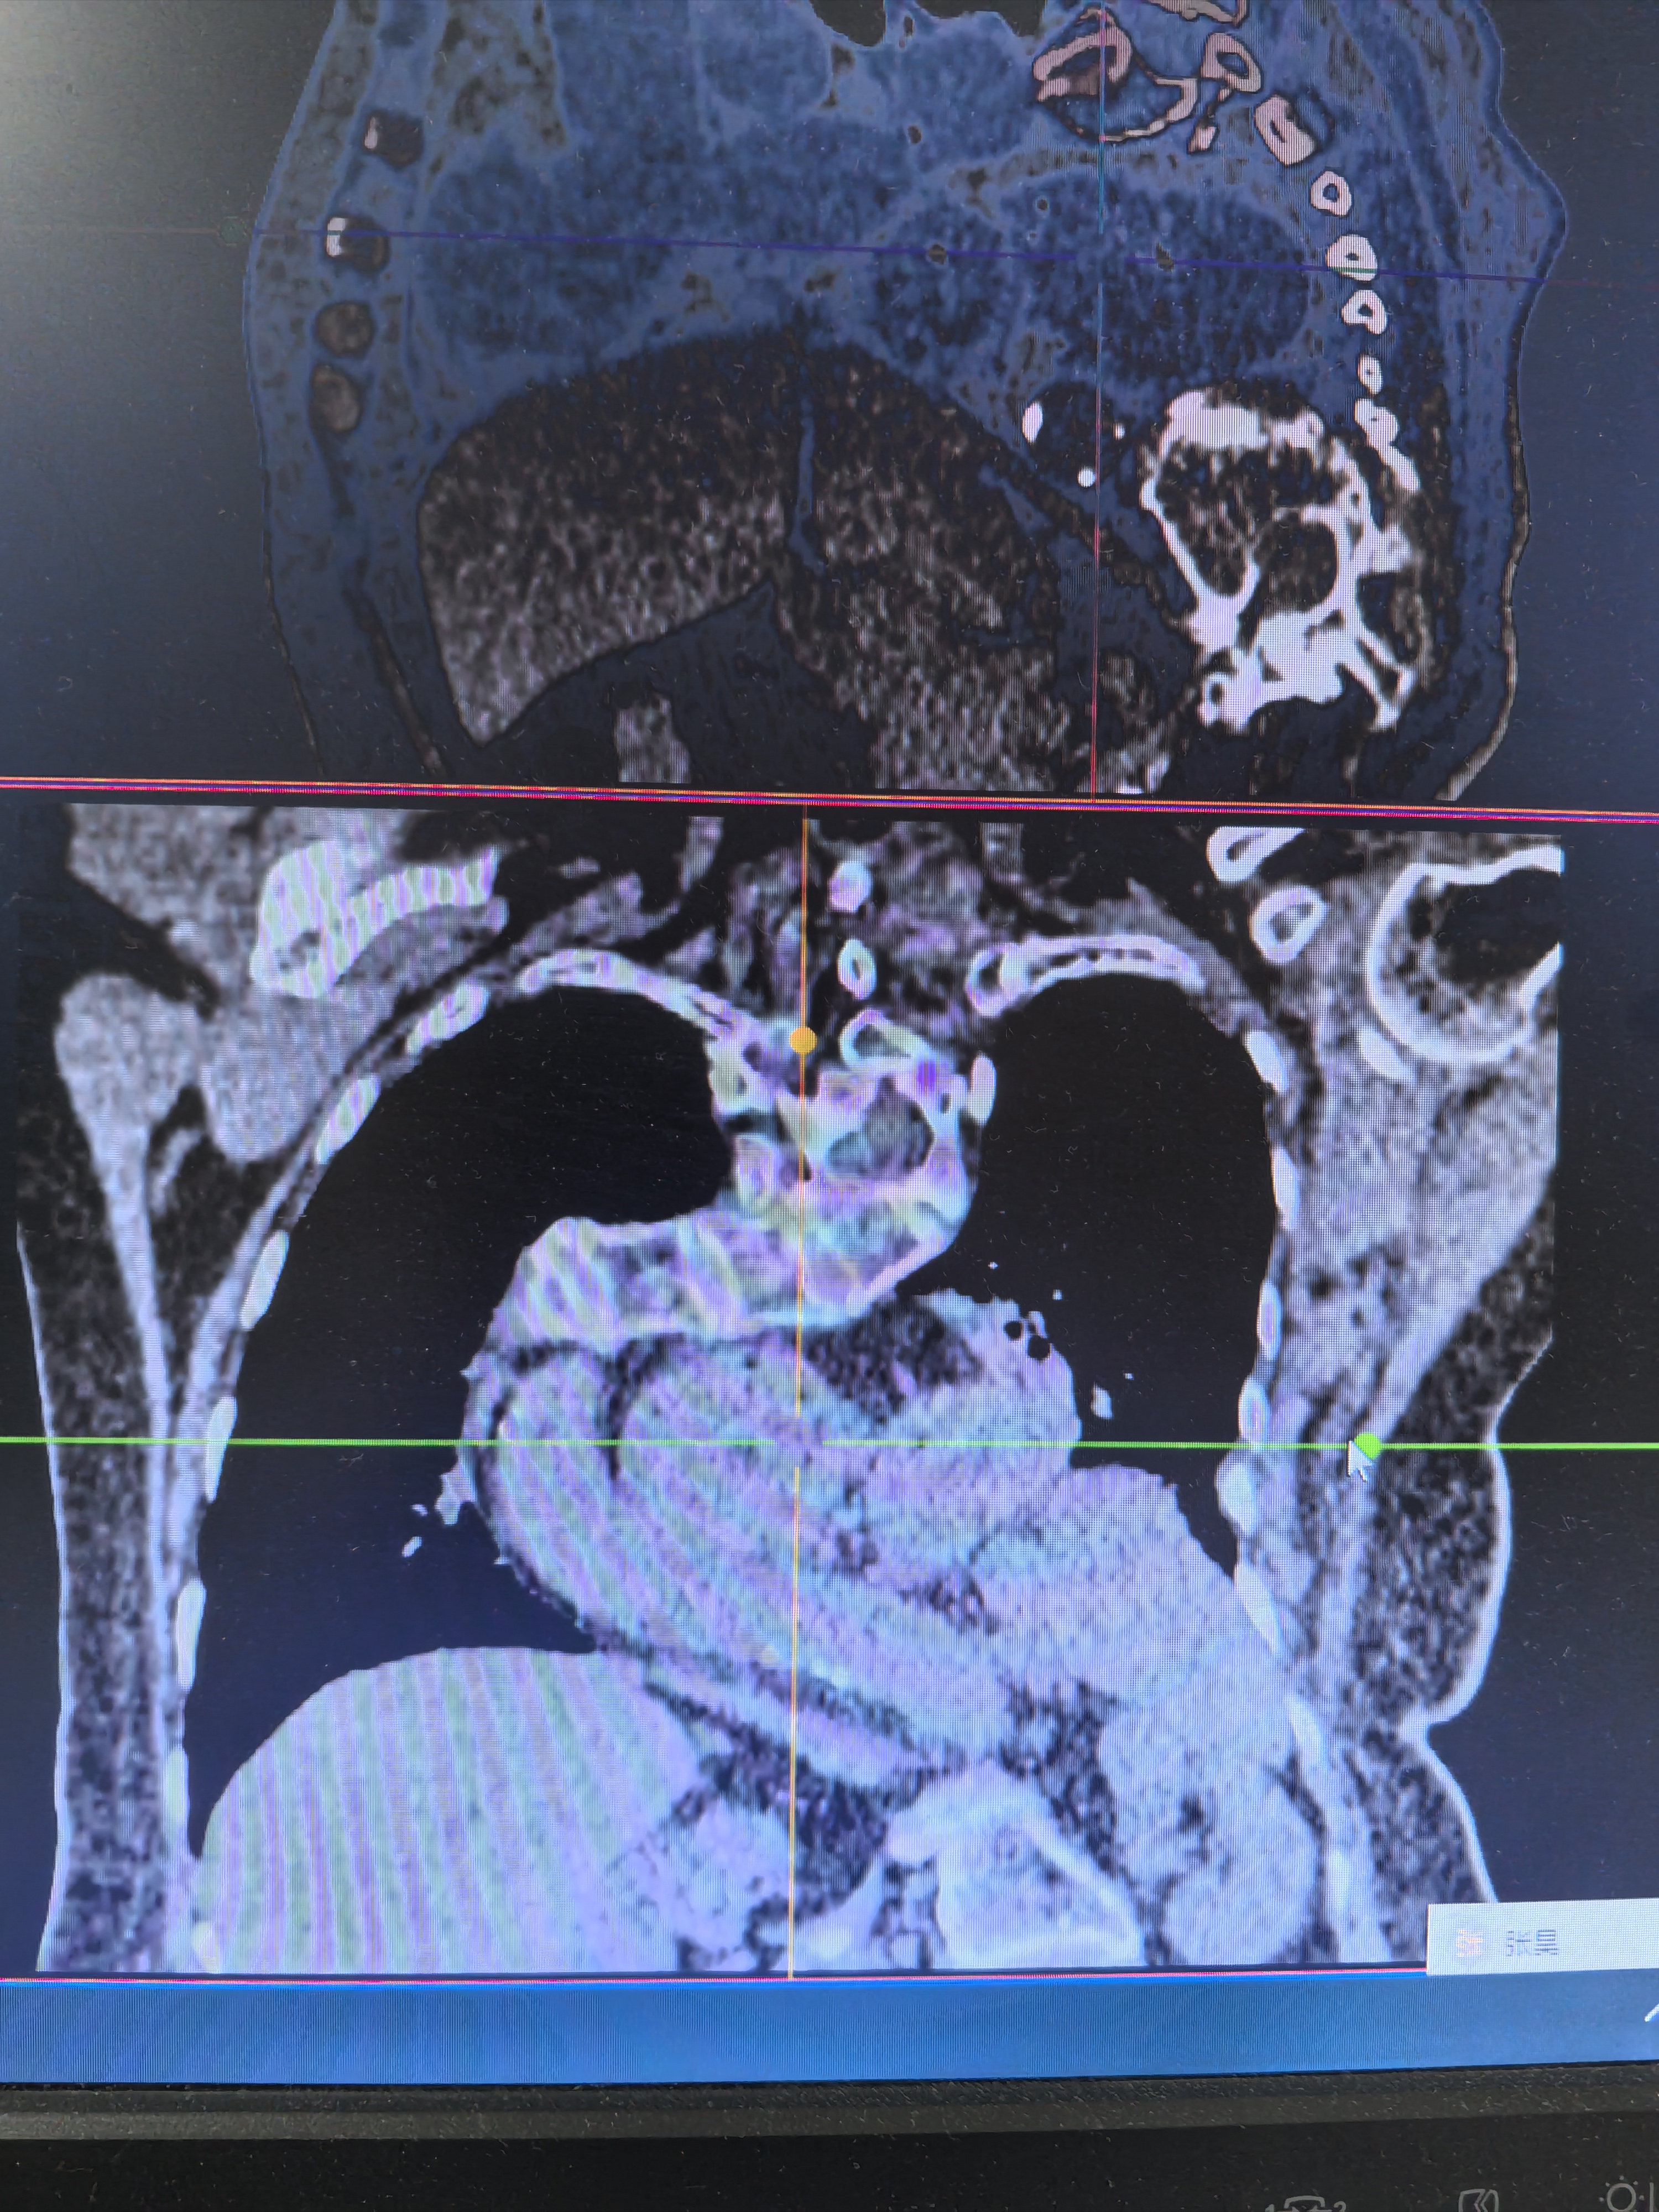

家住本地的患者晋女士,多年来被反复的反酸、烧心、胸痛等症状困扰,严重时甚至无法正常进食和睡眠。为了寻求有效治疗,她辗转于市内多家医院就诊。然而,由于其病情特殊——食管裂孔疝本就属于腹腔与胸腔交界部位的复杂疾病,还合并了严重的脊柱侧弯和胸廓畸形,胸腔腹腔解剖结构严重异常,手术难度极大,术中不仅要精准修复食管裂孔,还要兼顾畸形胸廓对手术视野的限制,稍有不慎便可能损伤周围重要脏器,多家医院经综合评估后,均表示难以开展手术,建议其转诊。

接诊后,总院派驻专家、外科梁燕凯主任梁带领的外科团队高度重视,第一时间组织多学科会诊。外科、手术麻醉科、心病科、肺病科等科室专家共同研讨,仔细分析患者的影像学资料,精准评估其解剖结构异常程度,充分考量手术风险与难点。针对患者脊柱侧弯、胸廓畸形导致的手术入路狭窄问题,团队最终制定了腹腔镜下食管裂孔疝修补+胃底折叠术的微创手术方案。术后,在医护团队的精心护理下,晋女士恢复迅速,反酸、烧心等症状彻底消失,饮食和睡眠逐步恢复正常,不久便可康复出院。